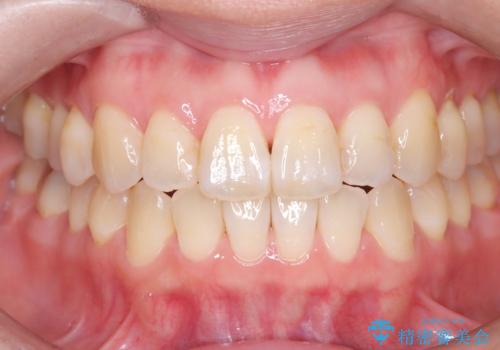

銀座平日限定のオフィスホワイトニングは、痛みが少なく自然な色味希望希望の方にお勧めです

歯の表面に多少の白濁はでていますが、色味のトーンが上がったため満足して頂きました